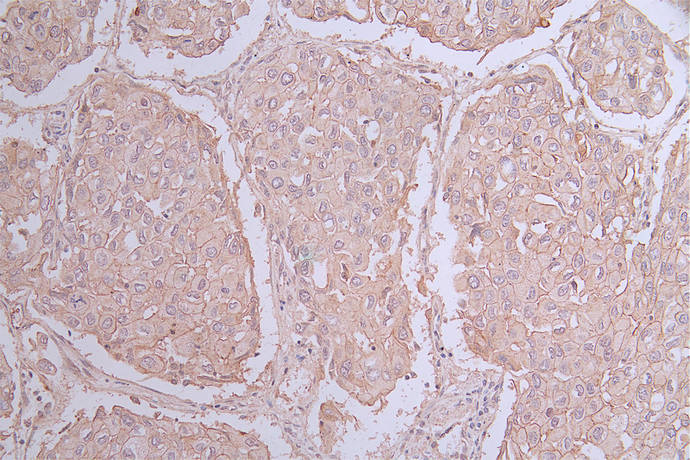

癌胚抗原相關細胞黏附分子1(CEACAM1),亦稱 CD66a 或膽管糖蛋白(BGP),屬于免疫球蛋白超家族,廣泛存在